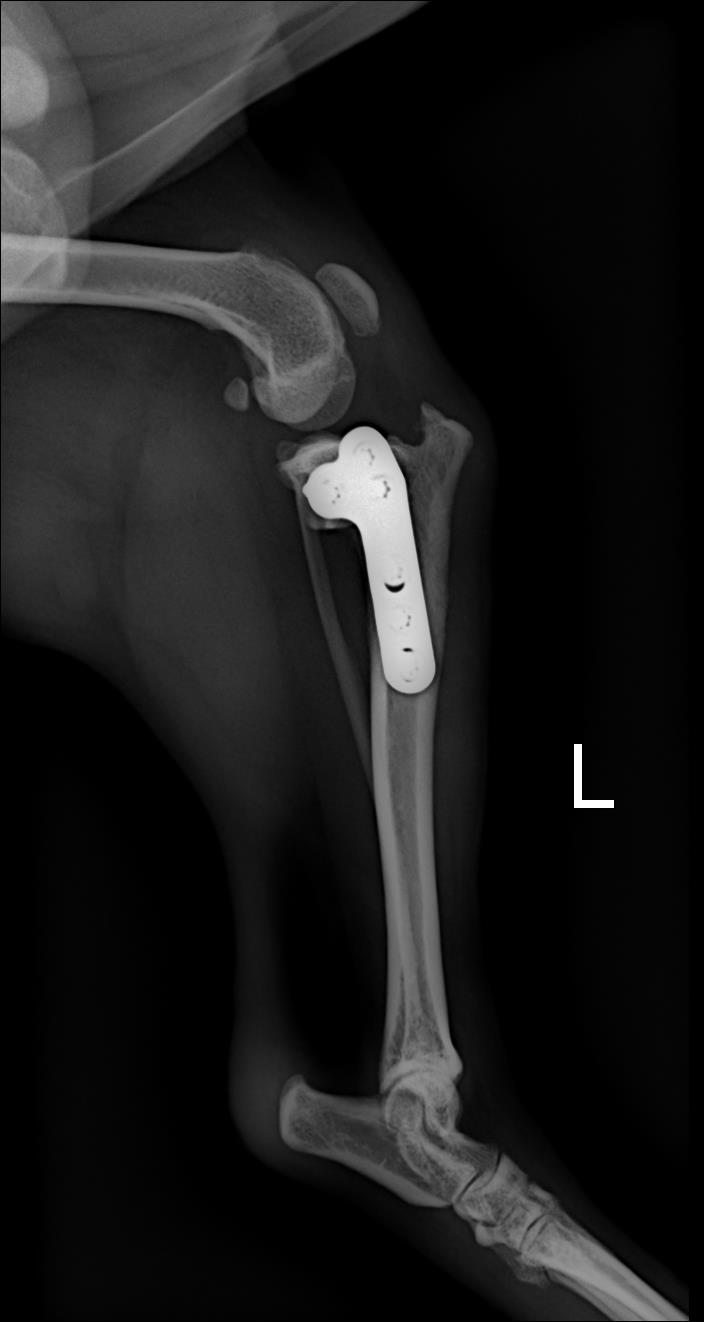

몽구4915 작성일전십자 인대수술 했는데, 수술이 잘돼서 너무 다행입니다️ 항상 친절하시고, 꼼꼼히 봐주셔서 신뢰가 가요~~